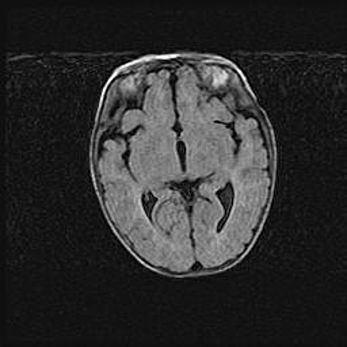

Множественные кисты обоих полушарий головного мозга, наибольшая из них в правой затылочной области. Ассиметричная атрофическая гидроцефалия.

Возраст: 7 месяцев

Вес: 5660 г

Пол: мужской

Окружность головы: 41,5 см

Срок гестации: 28-29 недель

Кисты головного мозга развиваются в результате многоочаговых некрозов вещества мозга и возникают вследствие перенесенной перинатальной инфекции, менингитов, энцефалитов, асфиксии, родовой травмы, расстройств мозгового кровообращения различного генеза. Образованию кист в веществе головного мозга плодов и новорожденных способствуют такие факторы, как высокое содержание в нем воды, недостаточная (или отсутствие) миелинизация и слабая астроглиальная реакция на повреждение.

Кисты могут сочетаться с гидроцефалией и другими поражениями головного мозга.